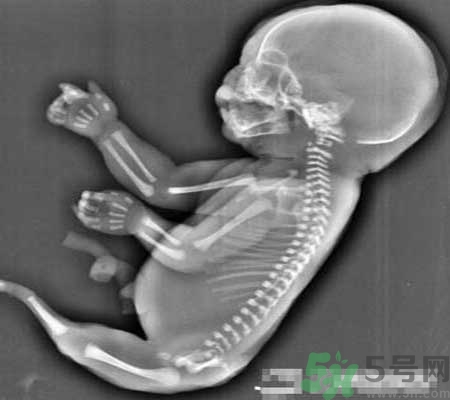

當(dāng)時(shí)經(jīng)超聲檢查發(fā)現(xiàn),孕婦宮腔內(nèi)未見羊水暗區(qū),借助胎兒骨骼影像順序連續(xù)掃查,發(fā)現(xiàn)胎兒頭顱、胸腔、雙上肢,也可以看到一個(gè)跳動(dòng)的心臟。但下肢只找到一條股骨,未見雙腿、膀胱,只有一側(cè)發(fā)育不良的腎臟。